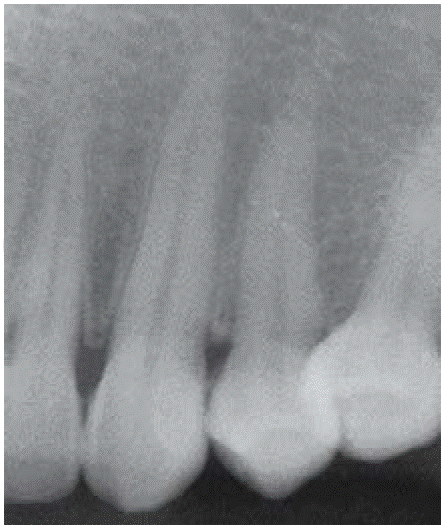

Clinical examination revealed an inflammatory gingival lesion at the level of teeth 3.4 and 3.5. Measuring approximately 15x9 mm. The lesion covered the vestibular side of the clinical crown, it was firm, lobulated, of rugged texture and bleeding upon stimulus (Figures 1and2). Periodontal assessment did not reveal periodontal pockets; presence of plaque was observed, and an O'Leary oral hygiene index of 18.75 was determined. Radiographic evaluation revealed absence of interproximal contact between teeth 3.4 and 3.5 as well as restorative material in the interproximal area (Figure 3).

Figure 3 Periapical X-ray of the lesion area. Absence of interproximal contact between teeth 3.4 and 3.5.